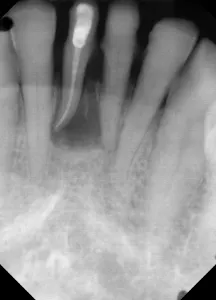

This patient presented with discomfort and mobile teeth Nos. 24 and 25. Extractions were performed, and the area was allowed to heal for six months. Mini-implants were placed in site Nos. 24 and 25 and immediately loaded with temporary crowns. The final splinted restoration was cemented two weeks later.

Figure 7: Following six months of healing